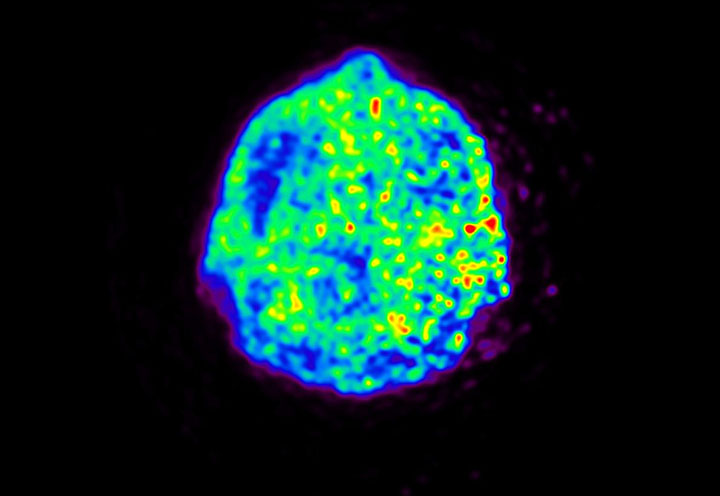

Head / Case5 : Amyloid

Courtesy : Kindai University Hospital

- Imaging protocol

- Injected dose: 4.27 MBq/kg, 18F-Flutemetamol

- Uptake time: 99 minutes

- Scan time: 20 minutes